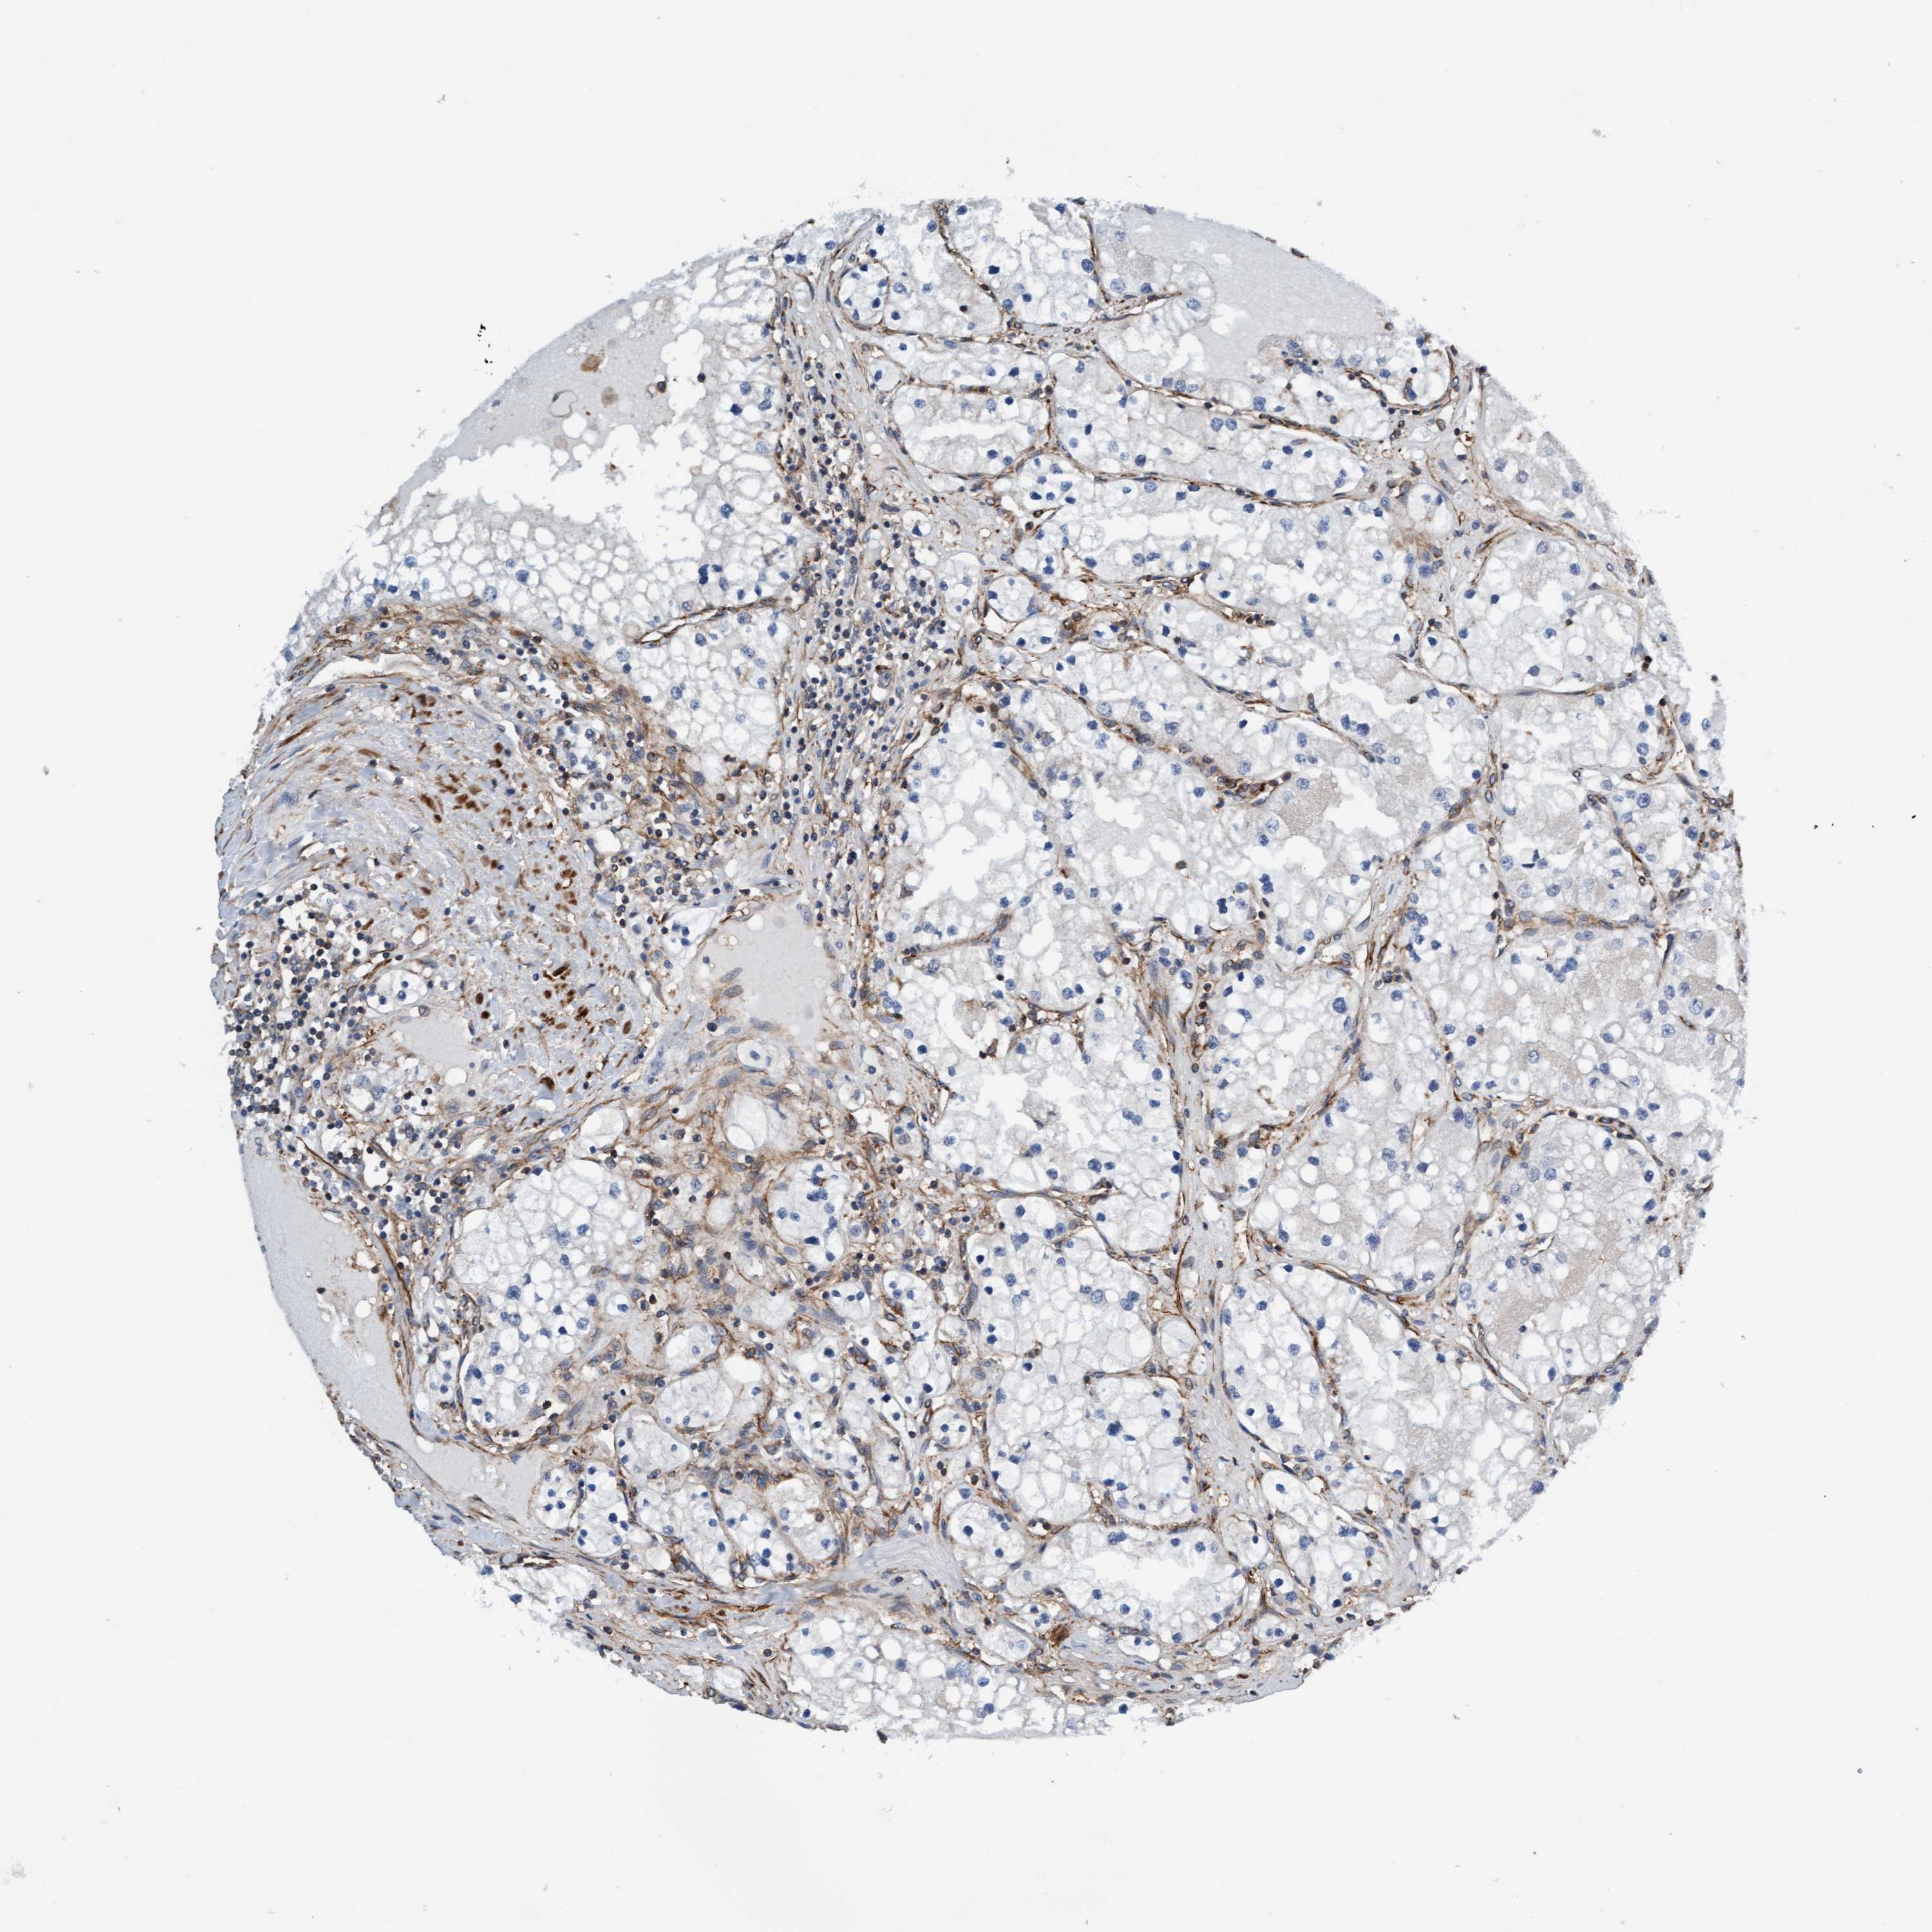

KIDNEY RENAL CLEAR CELL CARCINOMA (VALIDATION) - Interactive survival scatter ploti

The Survival Scatter plot shows the clinical status (i.e. dead or alive) for all individuals in the patient cohort, based on the same data that underlies the corresponding Kaplan-Meier plots. Patients that are alive at last time for follow-up are shown in blue and patients who have died during the study are shown in red.

The x-axis shows the expression levels (FPKM) of the investigated gene in the tumor tissue at the time of diagnosis. The y-axis shows the follow-up time after diagnosis (years). Both axes are complimented with kernel density curves demonstrating the data density over the axes. The top density plot shows the expression levels (FPKM) distribution among dead (red) and alive patients (blue). The right density plot shows the data density of the survived years of dead patients with high and low expression levels respectively, stratified using the cutoff indicated by the vertical dashed line through the Survival Scatter plot. This cutoff is automatically defined based on the FPKM cutoff that minimizes the p-score. The cutoff can be changed by dragging the vertical line or by entering a cutoff value in the square labeled "Current cut-off".

Under the Survival Scatter plot the p-score landscape (black curve; left axis) is shown together with dead median separation (red curve; right axis). Dead median separation is the difference in median mRNA expression between patients who have died with high and low expression, respectively. It is calculated as follows: median FPKM expression of dead patients with high expression - median FPKM expression of dead patients with low expression. This is intended to aid the user in visually exploring custom cutoffs and the associated p-scores and dead median separation.

Individual patient data is displayed and can be filtered by clicking on one or more of the category buttons on the top of the page. Categories describing expression level and patient information include: high, low, alive, dead, female, male and tumor stages. The scale of the x-axis can be toggled between linear and log-scale by clicking on the "x log" button. Mouse-over function shows TCGA ID, patient information and mRNA expression (FPKM) for each patient.

& Survival analysisi

Kaplan-Meier plots summarize results from analysis of correlation between mRNA expression level and patient survival. Patients were divided based on level of expression into one of the two groups "low" (under cut off) or "high" (over cut off). X-axis shows time for survival (years) and y-axis shows the probability of survival, where 1.0 corresponds to 100 percent.

FMNL3 is validated prognostic, high expression is favorable in Kidney Renal Clear Cell Carcinoma (validation)

Best expression cut offi

Based on the FPKM value of each gene, patients were classified into two groups and association between prognosis (survival) and gene expression (FPKM) was examined. The best expression cut-off refers the FPKM value that yields maximal difference with regard to survival between the two groups at the lowest log-rank P-value. Best expression cut-off was selected based on survival analysis .

When clicking on this number, the vertical dashed line indicating cut-off, the interactive survival plot, and the Kaplan-Meier curve will be adjusted to show results based on the best expression cut-off.

: 27.36

Average pTPM 23.2

Number of samples 100